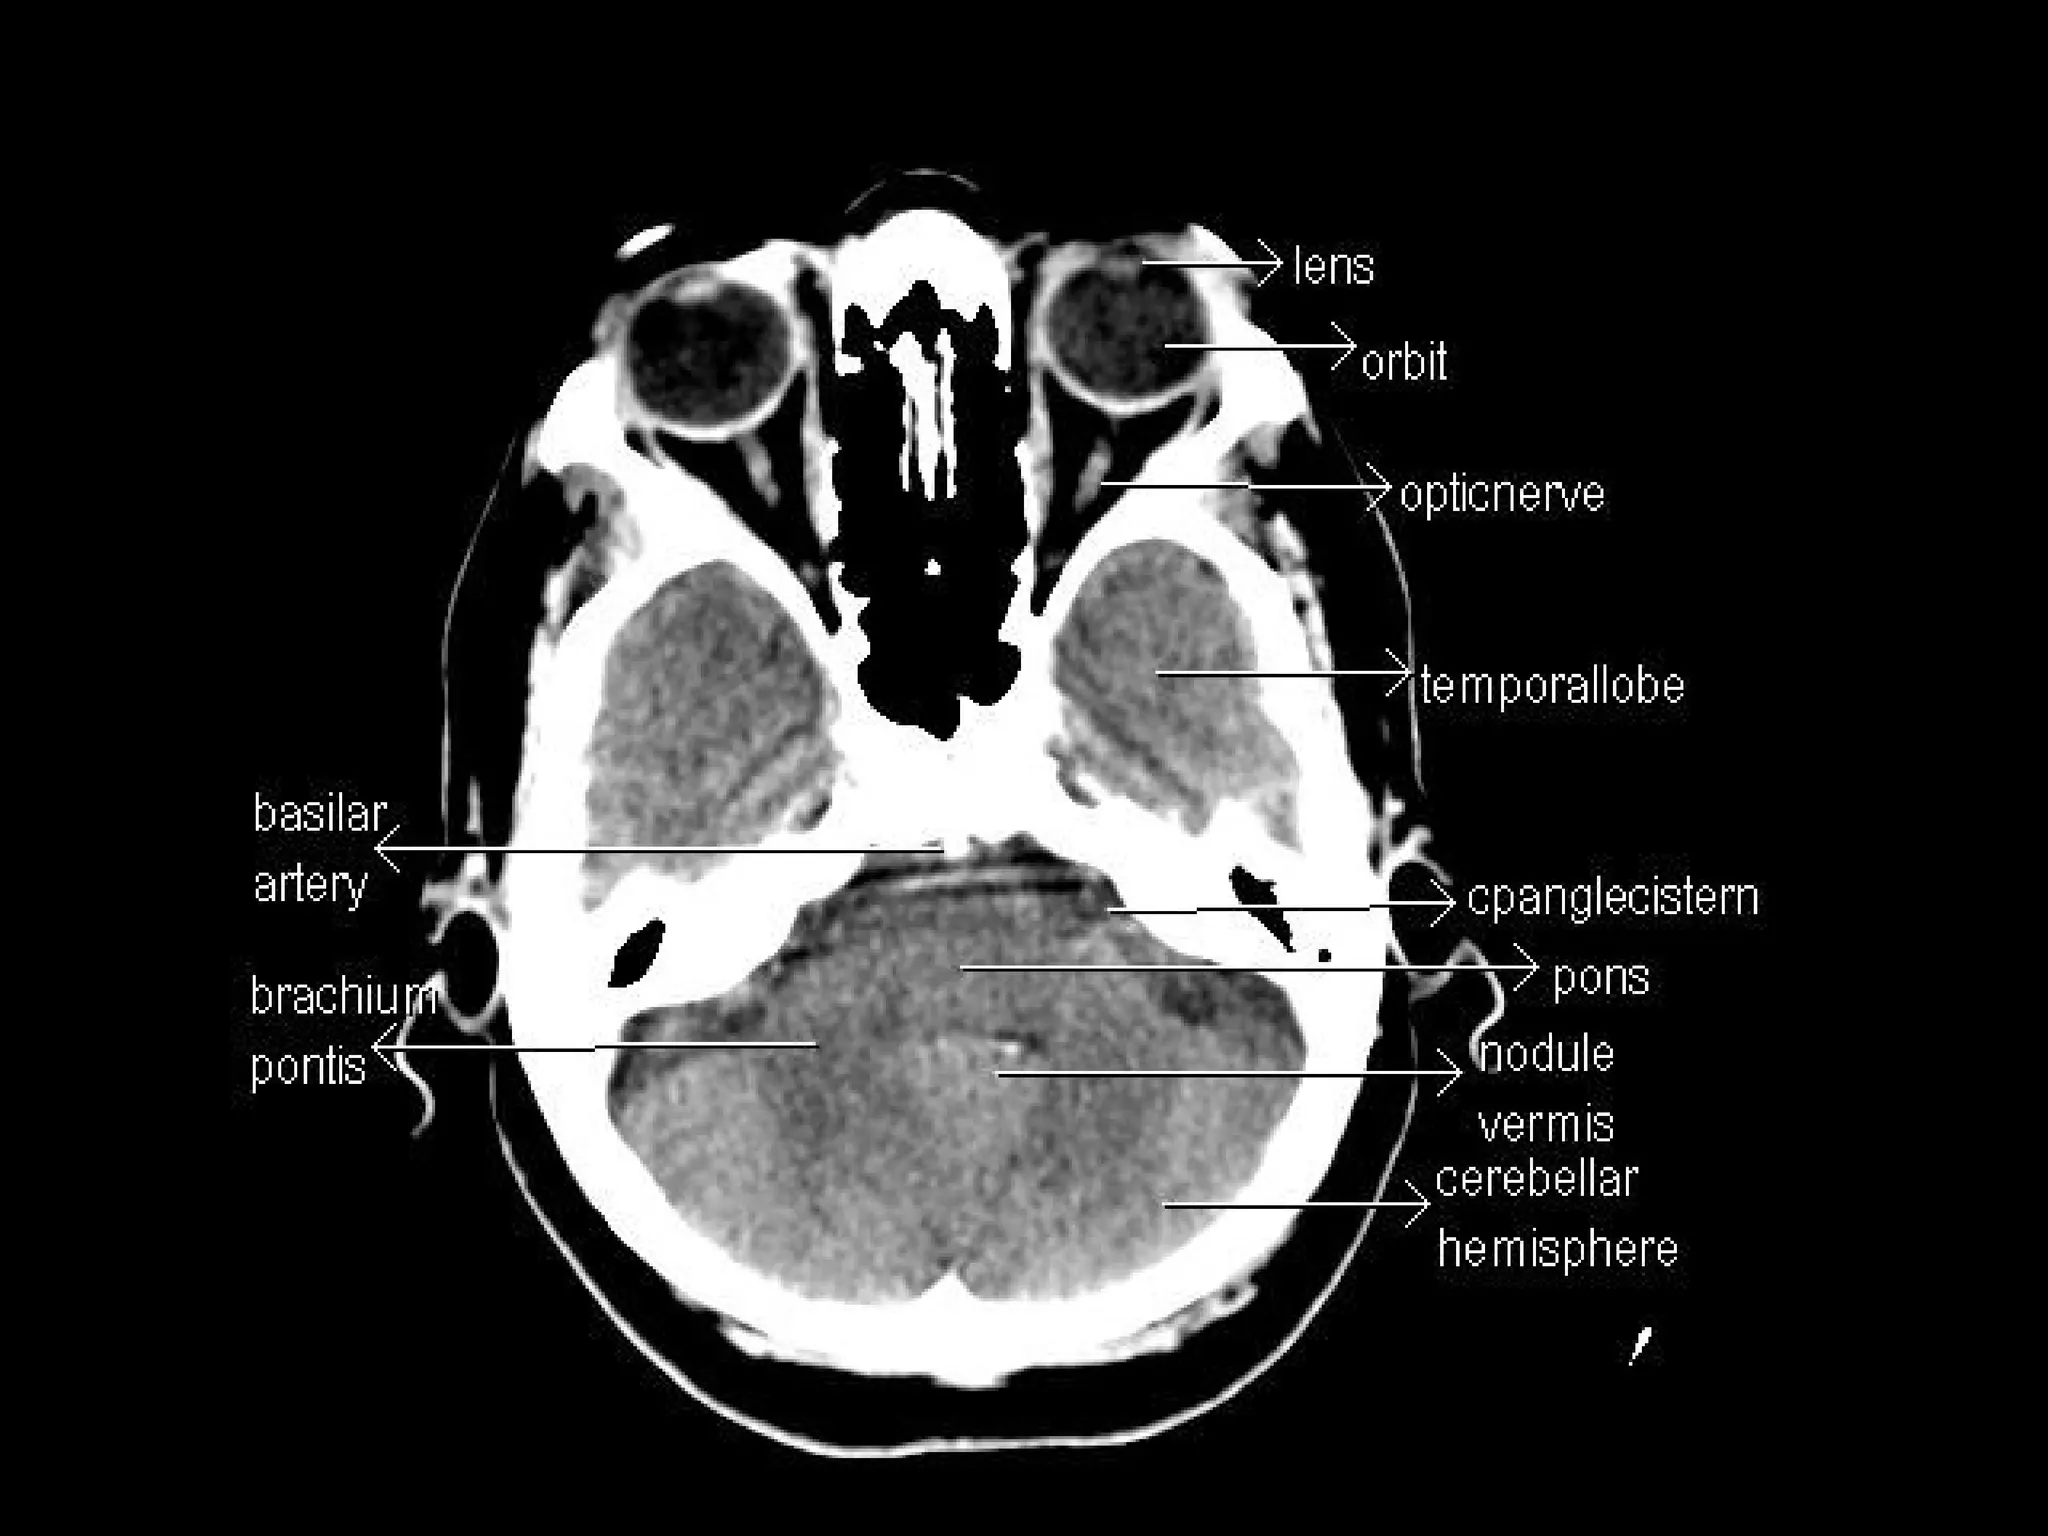

Radiographers are medical professionals who perform diagnostic imaging examinations and procedures to help physicians diagnose and treat diseases. They work under the supervision of radiologists to operate X-ray, CT, MRI, ultrasound and other medical imaging equipment and must have a strong understanding of human anatomy and pathology. Radiographers are responsible for correctly positioning patients, ensuring proper imaging techniques are used, and evaluating the quality of the resulting images.